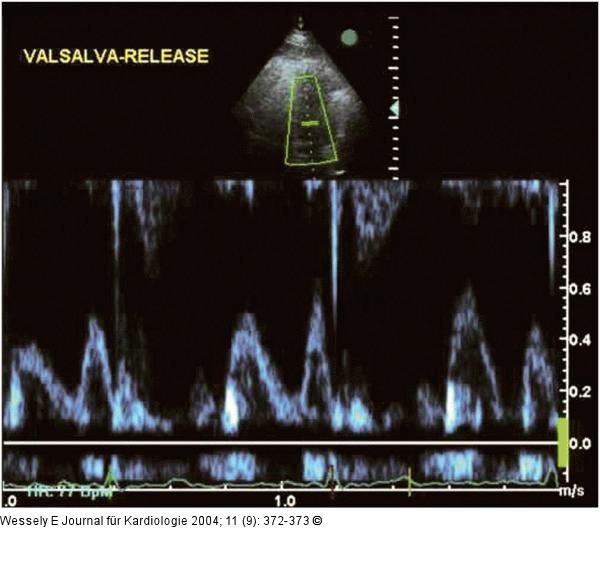

Abbildung 2: Diastolische Compliancestörung Apikaler Vierkammerblick, PW-Dopplersignal des Mitraleinstromes nach Valsalva-Manöver |

Apikaler Vierkammerblick, PW-Dopplersignal des Mitraleinstromes nach Valsalva-Manöver |